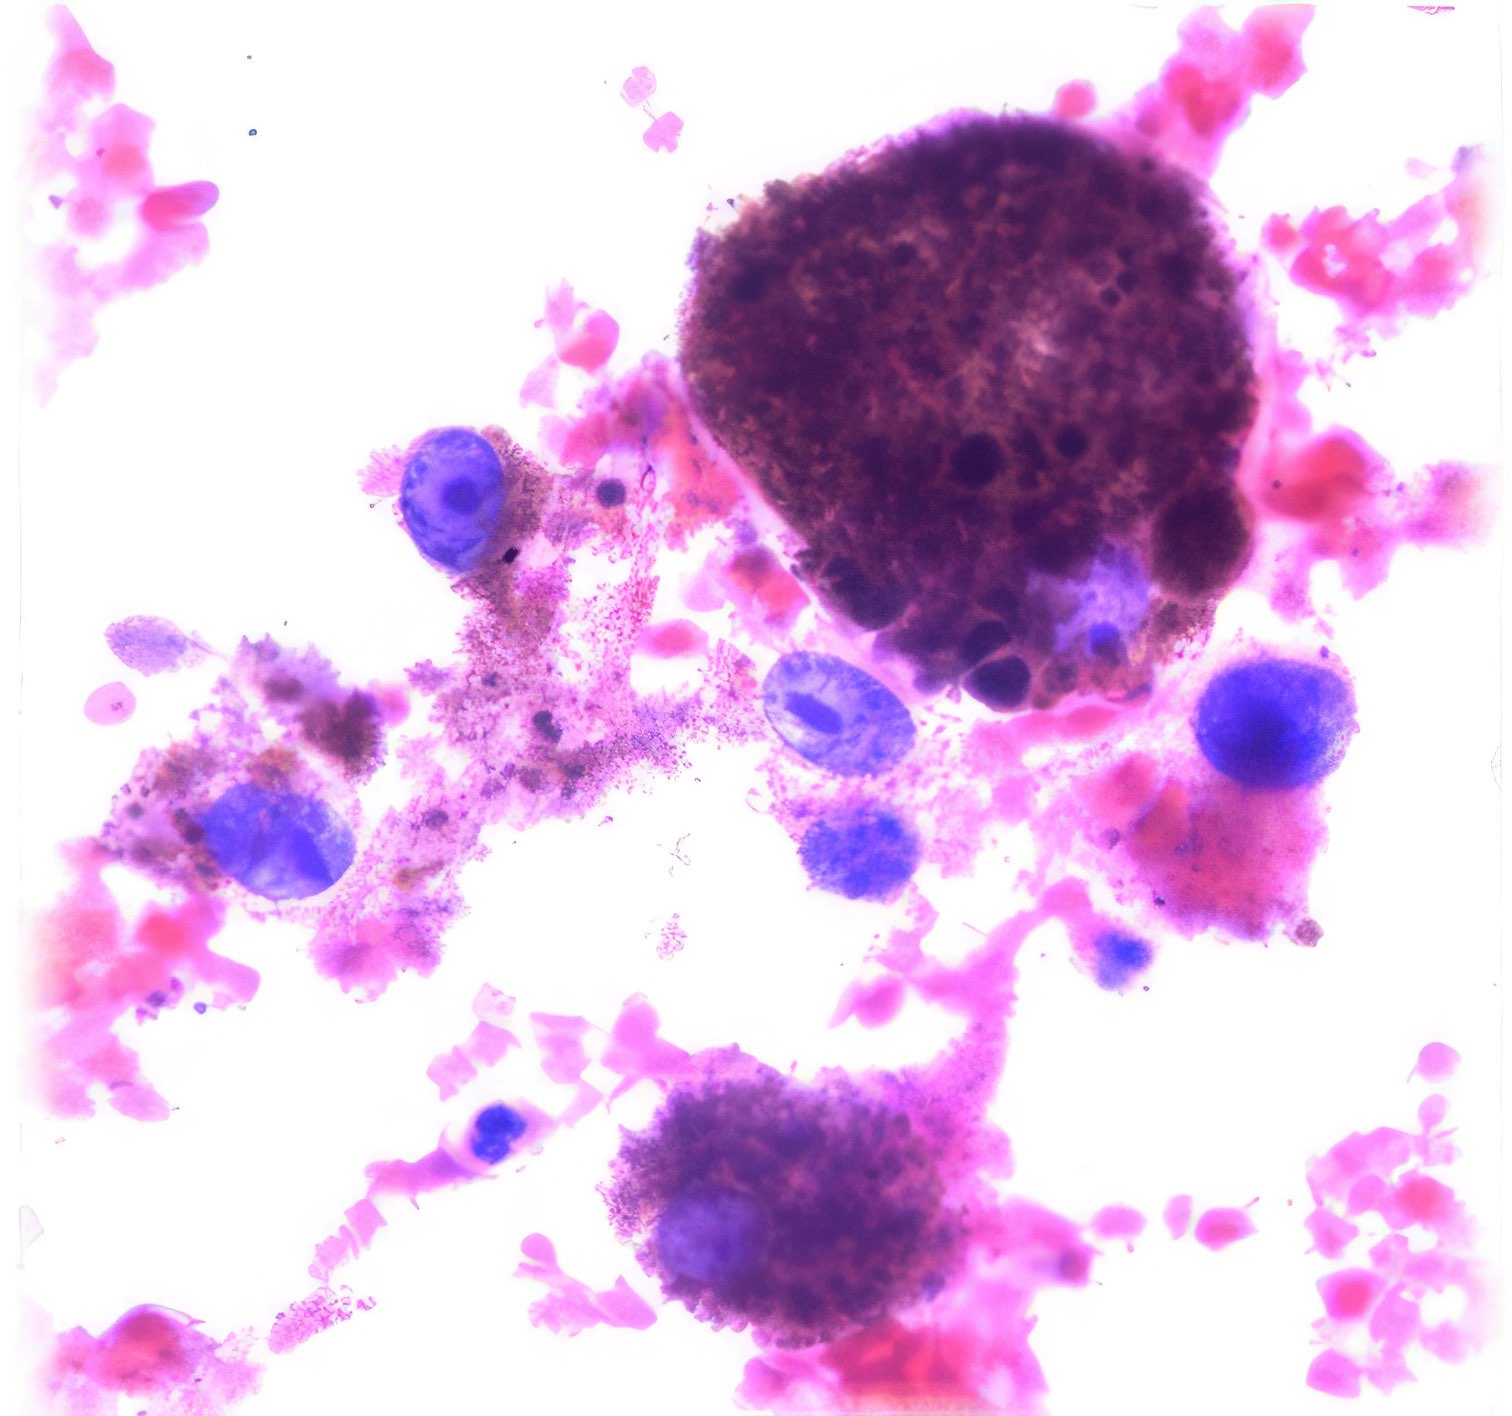

(Abbildungen 3 - 6: Pap, Vergrößerung 1000x)

Morbus Paget

Makroskopisch zeigt die areoläre Haut (Brustwarzenhof) eine feine ekzemartige nässende granuläre Struktur; die Brustwarze ist nicht eingezogen (Abb. 1 und 2). Die extrem atypischen Zellen liegen verstreut (Abb. 3), oder bilden lose zusammenhängende Gruppen (Abb. 4, 6). Einige sind doppelkernig. Im Vergleich zum gewöhnlichen Mammakarzinom sind sie extrem pleomorph und ihre Kerne sind stärker hyperchromatisch, sehr grob strukturiert, und zeigen manchmal prominente Chromozentren. Das Zytoplasma ist unterschiedlich breit und erscheint manchmal als vakuolär.

Histologie

Das durch Stanzbiopsie gewonnene histologische Präparat zeigt viele große, scheinbar vakuolisierte Zellen innerhalb des Plattenepithels. Eine PAS-Färbung war nicht möglich.

Differenzialdiagnose

Die zytologischen und histologischen Befunde sind charakteristisch für das Paget-Syndrom. Histologisch würden die Zellen PAS-positiv sein. Das Brustödem, die nicht eingezogene Brustwarze und die axilläre Schwellung weisen auf ein tiefsitzendes Karzinom hin, das bereits in die axillären Lymphknoten metastasiert hat. Die Kombination von Karzinom und Morbus Paget ist nicht ungewöhnlich 1. - Die extrem atypischen Zellen können zu einer Verwechslung mit einem Plattenepithelkarzinom führen 2. Andererseits unterscheidet dies die Zellen des Morbus Paget von denen des Adenoms, das ebenfalls in der areolären Region auftritt 3, 4. Schließlich können die makroskopisch erscheinenden vesikulären Strukturen einen Pemphigus vulgaris, eine Autoimmunerkrankung der Haut, simulieren 5.